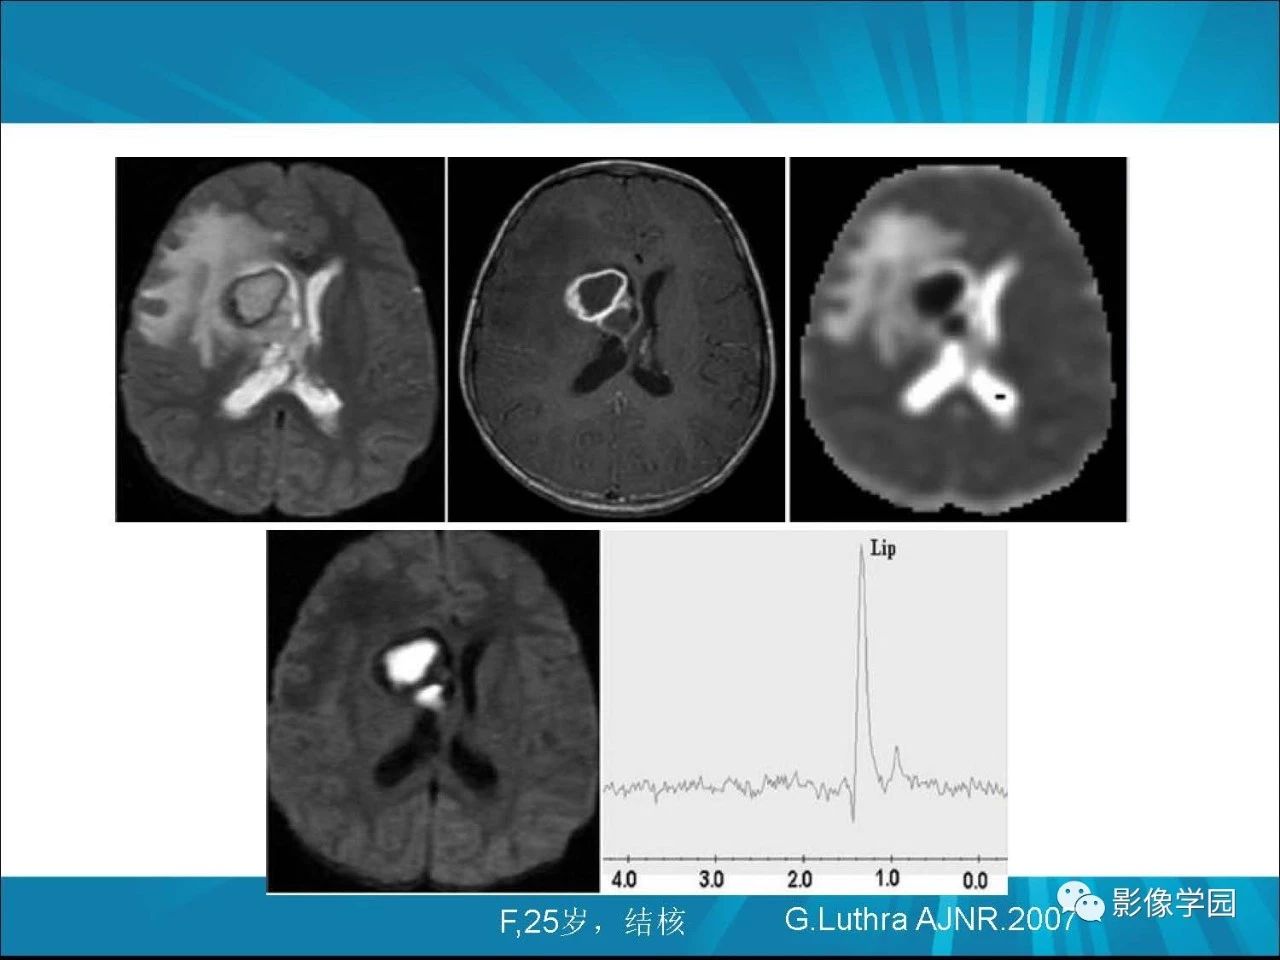

颅内环形强化病变的诊断思路

颅内环形强化病变的诊断思路中南大学湘雅二医院